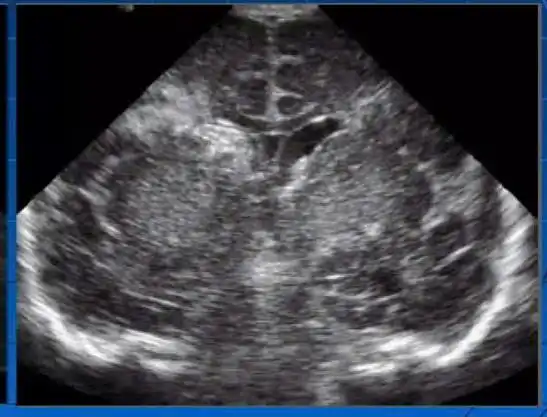

Một số hình ảnh tổn thương não phát hiện qua siêu âm thóp